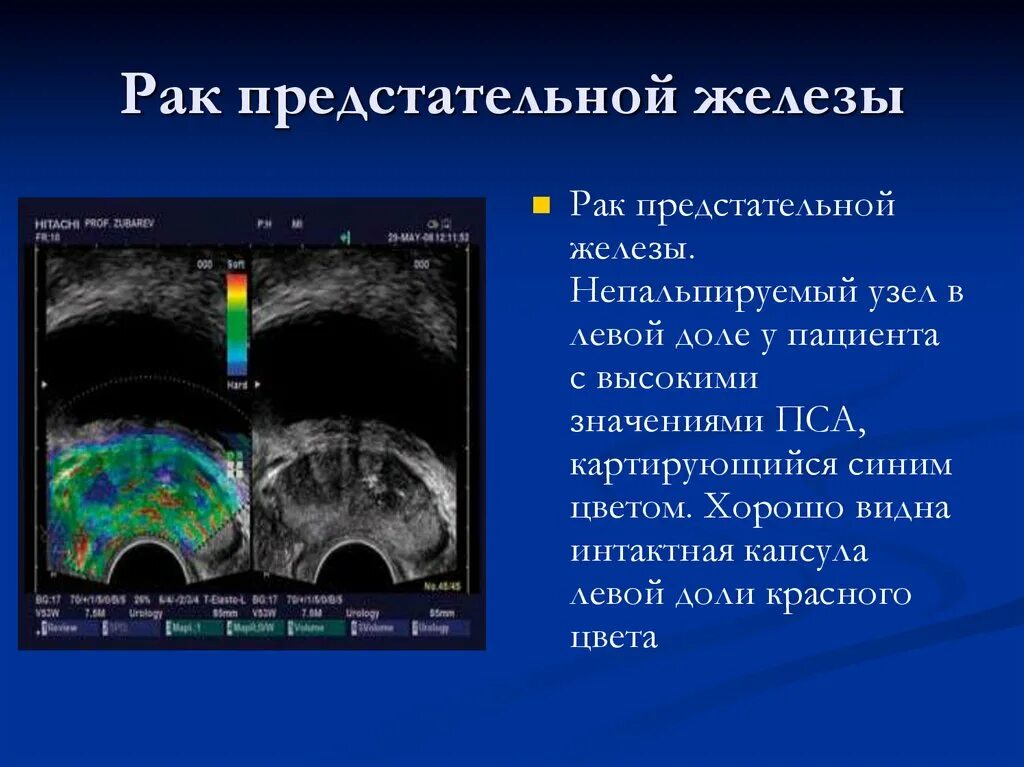

Злокачественная опухоль предстательной железы. Злокачественные новообразования простаты. Генная терапия злокачественных опухолей. Генная терапия в онкологии Карцинома предстательной железы УЗИ. Допплерография предстательной железы. Онкология предстательной железы

Карцинома предстательной железы УЗИ. Допплерография предстательной железы. Онкология предстательной железы Злокачественное новообразование предстательной железы. Карцинома предстательной железы. Susp BL предстательной железы что это. Tumor предстательной железы

Карцинома 4 степени предстательной железы. Онкология предстательной железы. Опухоль предстательной железы стадии Эластография предстательной железы. Компрессионная эластография предстательной железы. УЗИ С эластографией предстательной железы. Образование предстательной железы УЗИ

Эластография предстательной железы. Компрессионная эластография предстательной железы. УЗИ С эластографией предстательной железы. Образование предстательной железы УЗИ Опухоль предстательной железы. Злокачественное новообразование предстательной железы. Карцинома предстательной железы. Tumor предстательной железы